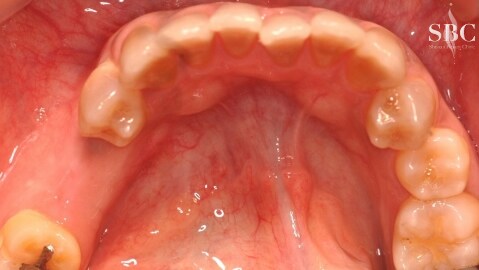

No.53663【インプラント・歯科その他】OSSTEMインプラント

施術前

術前